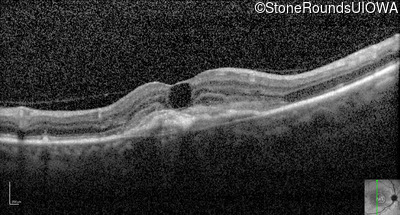

Optical Coherence Tomography - Right - 20/250

Exemplar / OCT Stack

Infrared Fundus Photograph - Right - 20/250

Exemplar